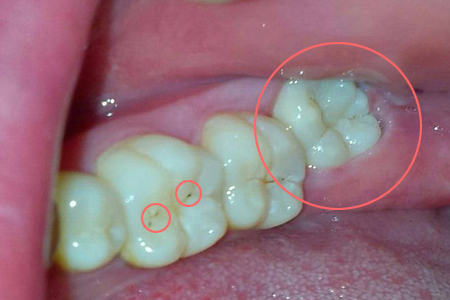

智齿是一颗很麻烦的牙齿,由于现代人的牙床都有不同程度的萎缩而无足够的位置容纳它。它就因此常常生出各种事端,引发冠周炎、龋病、挤歪邻牙。

3、出现龋病或会导致牙列不齐的。